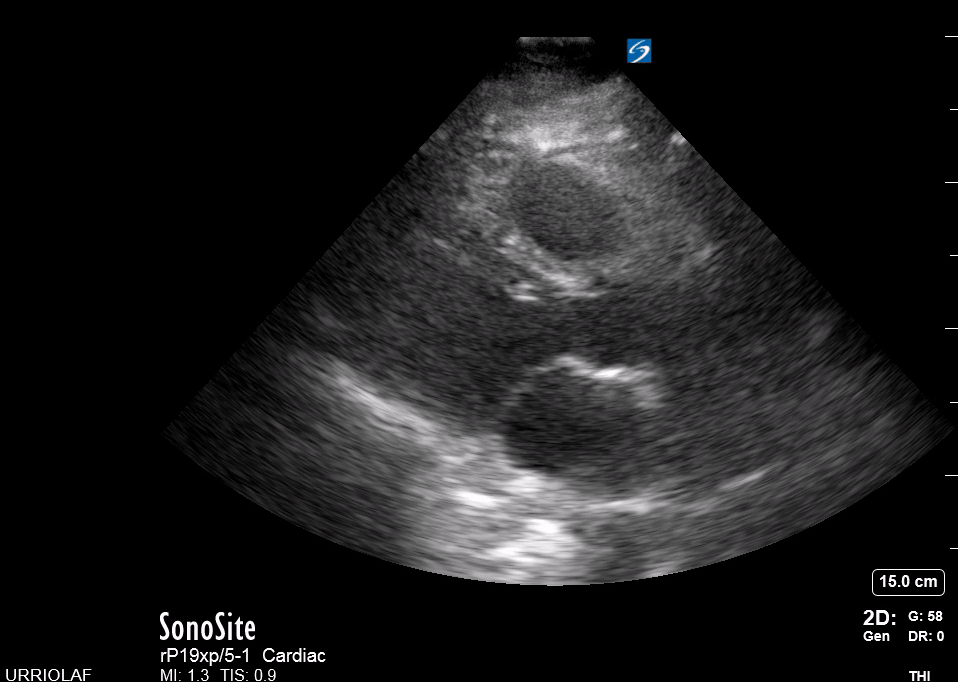

As the transverse (short-axis) images show the relative wall thickness and contractility, this view is the best for assessing regional wall motion. Also, the inferior portion of the view (papillary muscles) is ideal for comparing the relative size of both ventricles. In expert hands, the superior portion of the view allows evaluation of the aortic valve and RV overload.

ORIENTATION & TECHNIQUE

A good PSAX starts from a proper parasternal long-axis. Without sliding or displacing the probe, rotate it 90º clockwise so the marking points to the left shoulder. The resulting image is a transverse cut to the heart’s long axis, hence, a short-axis view.

While maintaining the short axis, sweep or gently fan the probe along the long axis to obtain a series of ‘sectional’ views of the LV and RV.